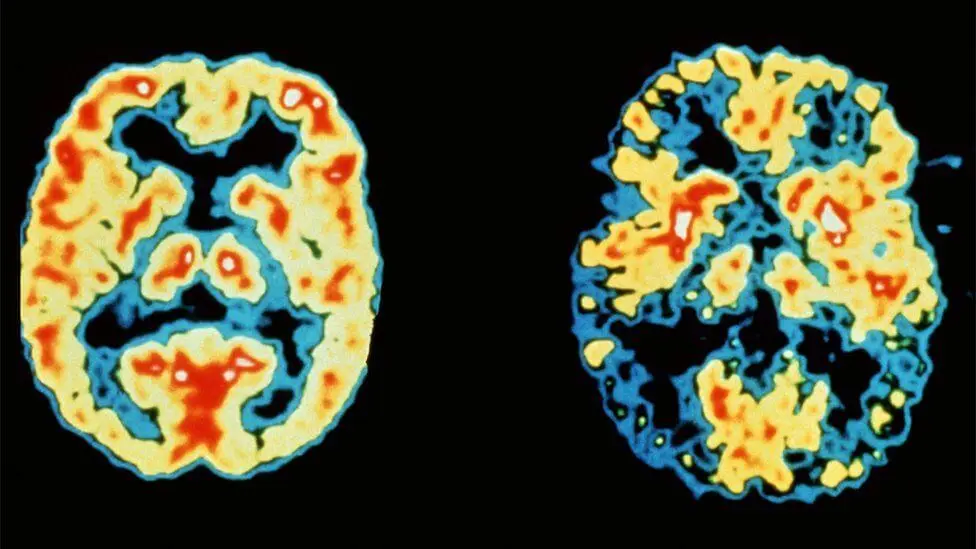

How dementia develops

Above:A 68-year-old woman with a 10-year history of cognitive impairment showed marked hypometabolism with a pattern suggestive of Alzheimer's disease prior to PET scan, PET scan after treatment with inhibitor (RI). Gradually approaching the normal brain, the patient's cognitive ability improved significantly.